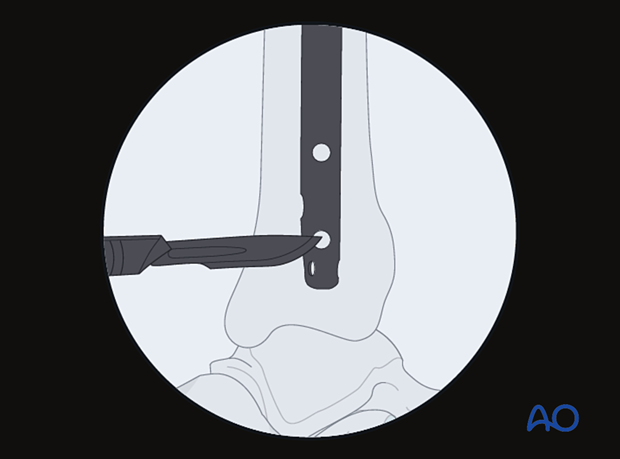

The leg must be positioned so that precise images can be obtained. In order to avoid malreduction of the fracture, it is best to move the fluoroscope around the tibia to obtain appropriate AP and lateral images of the distal end of the tibia. The leg is elevated on folded linen or other material and carefully supported to maintain the desired reduction (length, rotation and angulation). It is very important to confirm reduction (especially rotation) prior to cross bolt fixation. The C-arm is positioned to permit imaging while the entry site is located and drilled. Leave enough room for instruments between the image source and the patient’s leg.

The central ray of the fluoroscope must pass through the locking hole so that its image is perfectly round and centered on the display screen. This confirms that the central ray is perpendicular to the nail.

With the leg and fluoroscope properly positioned, an incision is made with radiographic guidance over the selected locking hole. Then the soft tissues are bluntly spread.

The drill tip is positioned over the center of the locking hole.

The drill tip must be aligned with the fluoroscopic central ray. The drill is then advanced through the near tibial cortex, the locking hole in the nail, and the far tibial cortex. Its position is confirmed radiographically. If correct, screw length is measured, the appropriate screw is inserted, and its proper placement is confirmed radiographically.